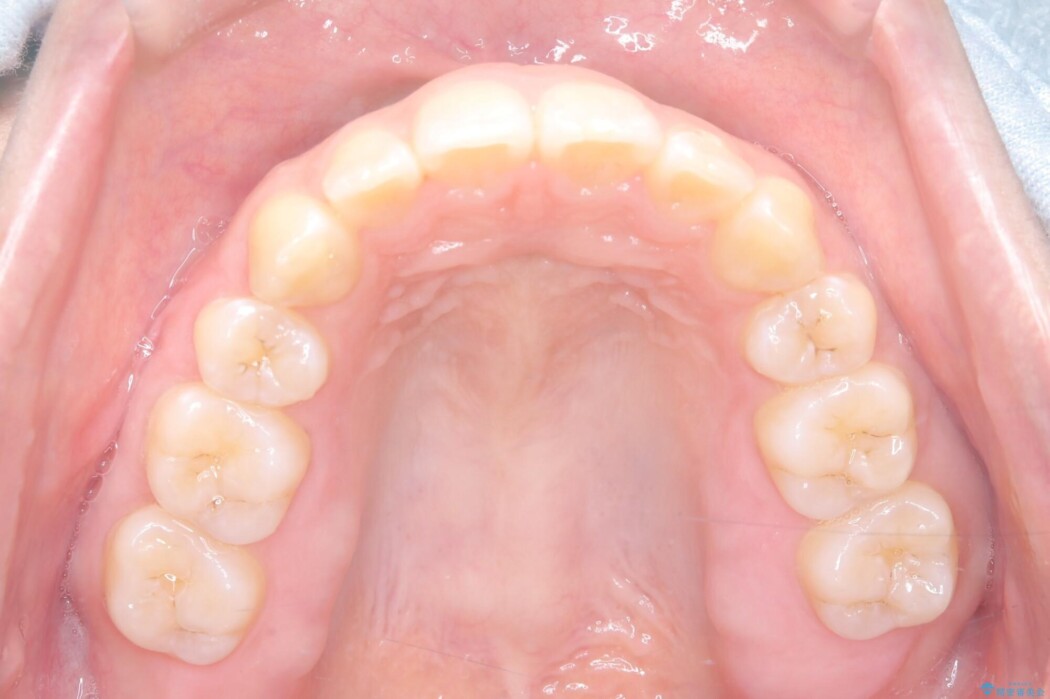

抜歯で得たスペースを活用し、大きく傾いた前歯の角度を修正しながら、ゆっくりと後方へ移動させていきました。

抜歯スペースが閉じるにつれて、唇側の圧迫感が解消され、口元のボリュームが自然に抑えられていきました。

治療後は、口元の突出感が解消され、鼻先から顎先を結ぶ「Eライン」が劇的に変化し「自信を持って笑えるようになった」と大変喜んでいただけました。